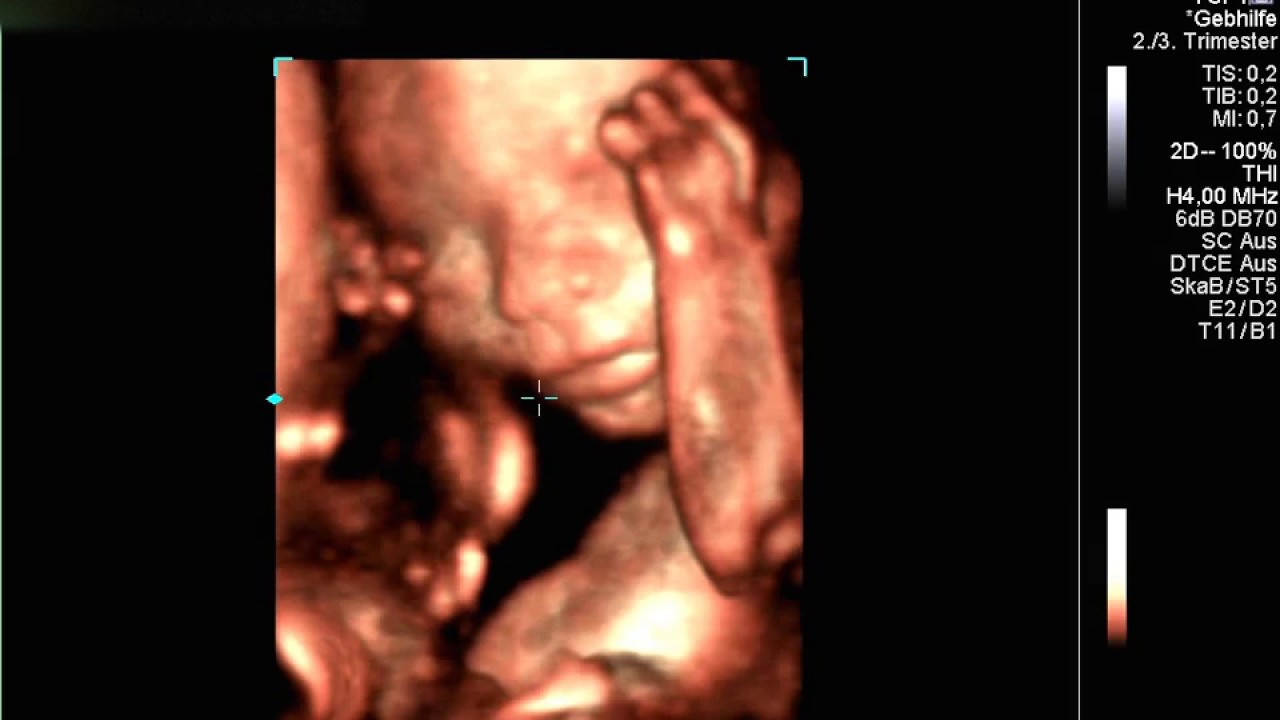

Sollten noch Befundergebnisse offen sein, oder sie sonst spezifische Fragen zu Verhütung, Schwangerschaft oder Medikamenten an Herr Dr. Pötsch haben, können sie uns gerne jederzeit telefonisch erreichen.